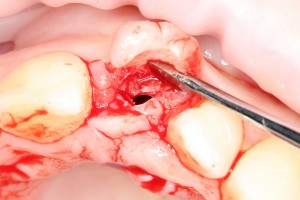

Итак, позиционируем имплантат. Для начала, с помощью пина:

Напомню правило позиционирования в области фронтальной группы зубов:

Ось импланта выходит на небную поверхность будущей коронки. Или, в крайнем случае, на режущий край.

На позиционировании имплантов делается наибольшее количество имплантологических ошибок, поэтому, если с этим есть сложности, я рекомендую использовать хирургические шаблоны. Благо, сейчас их предлагают повсеместно.

Лунка готова, устанавливаем имплантат:

Это Nobel Replace CC 3.5×13 mm. Оптимальный размер импланта для работы в этом клиническом случае.